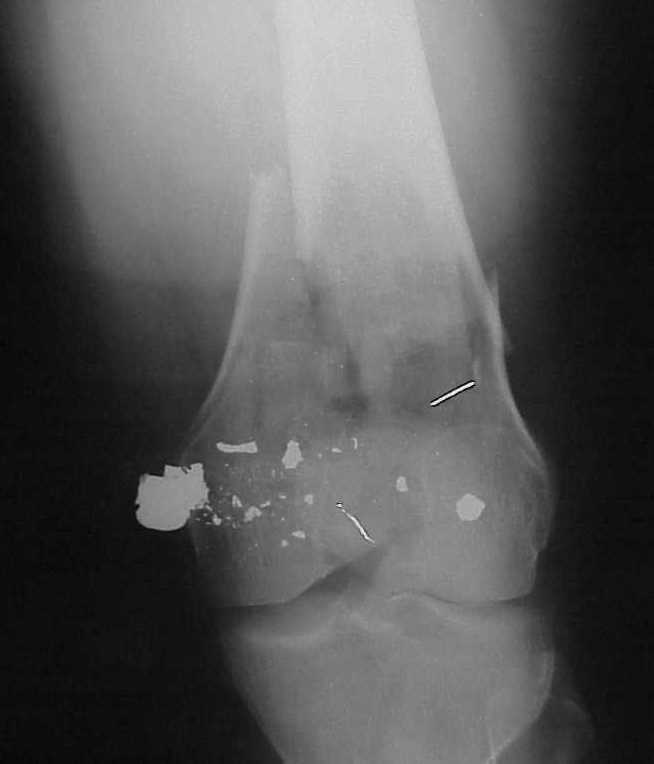

See attached case that was done several years ago before LISS. He had comminuted trochlea and anterior blocking screws were used to prevent anterior IMN cut-out.